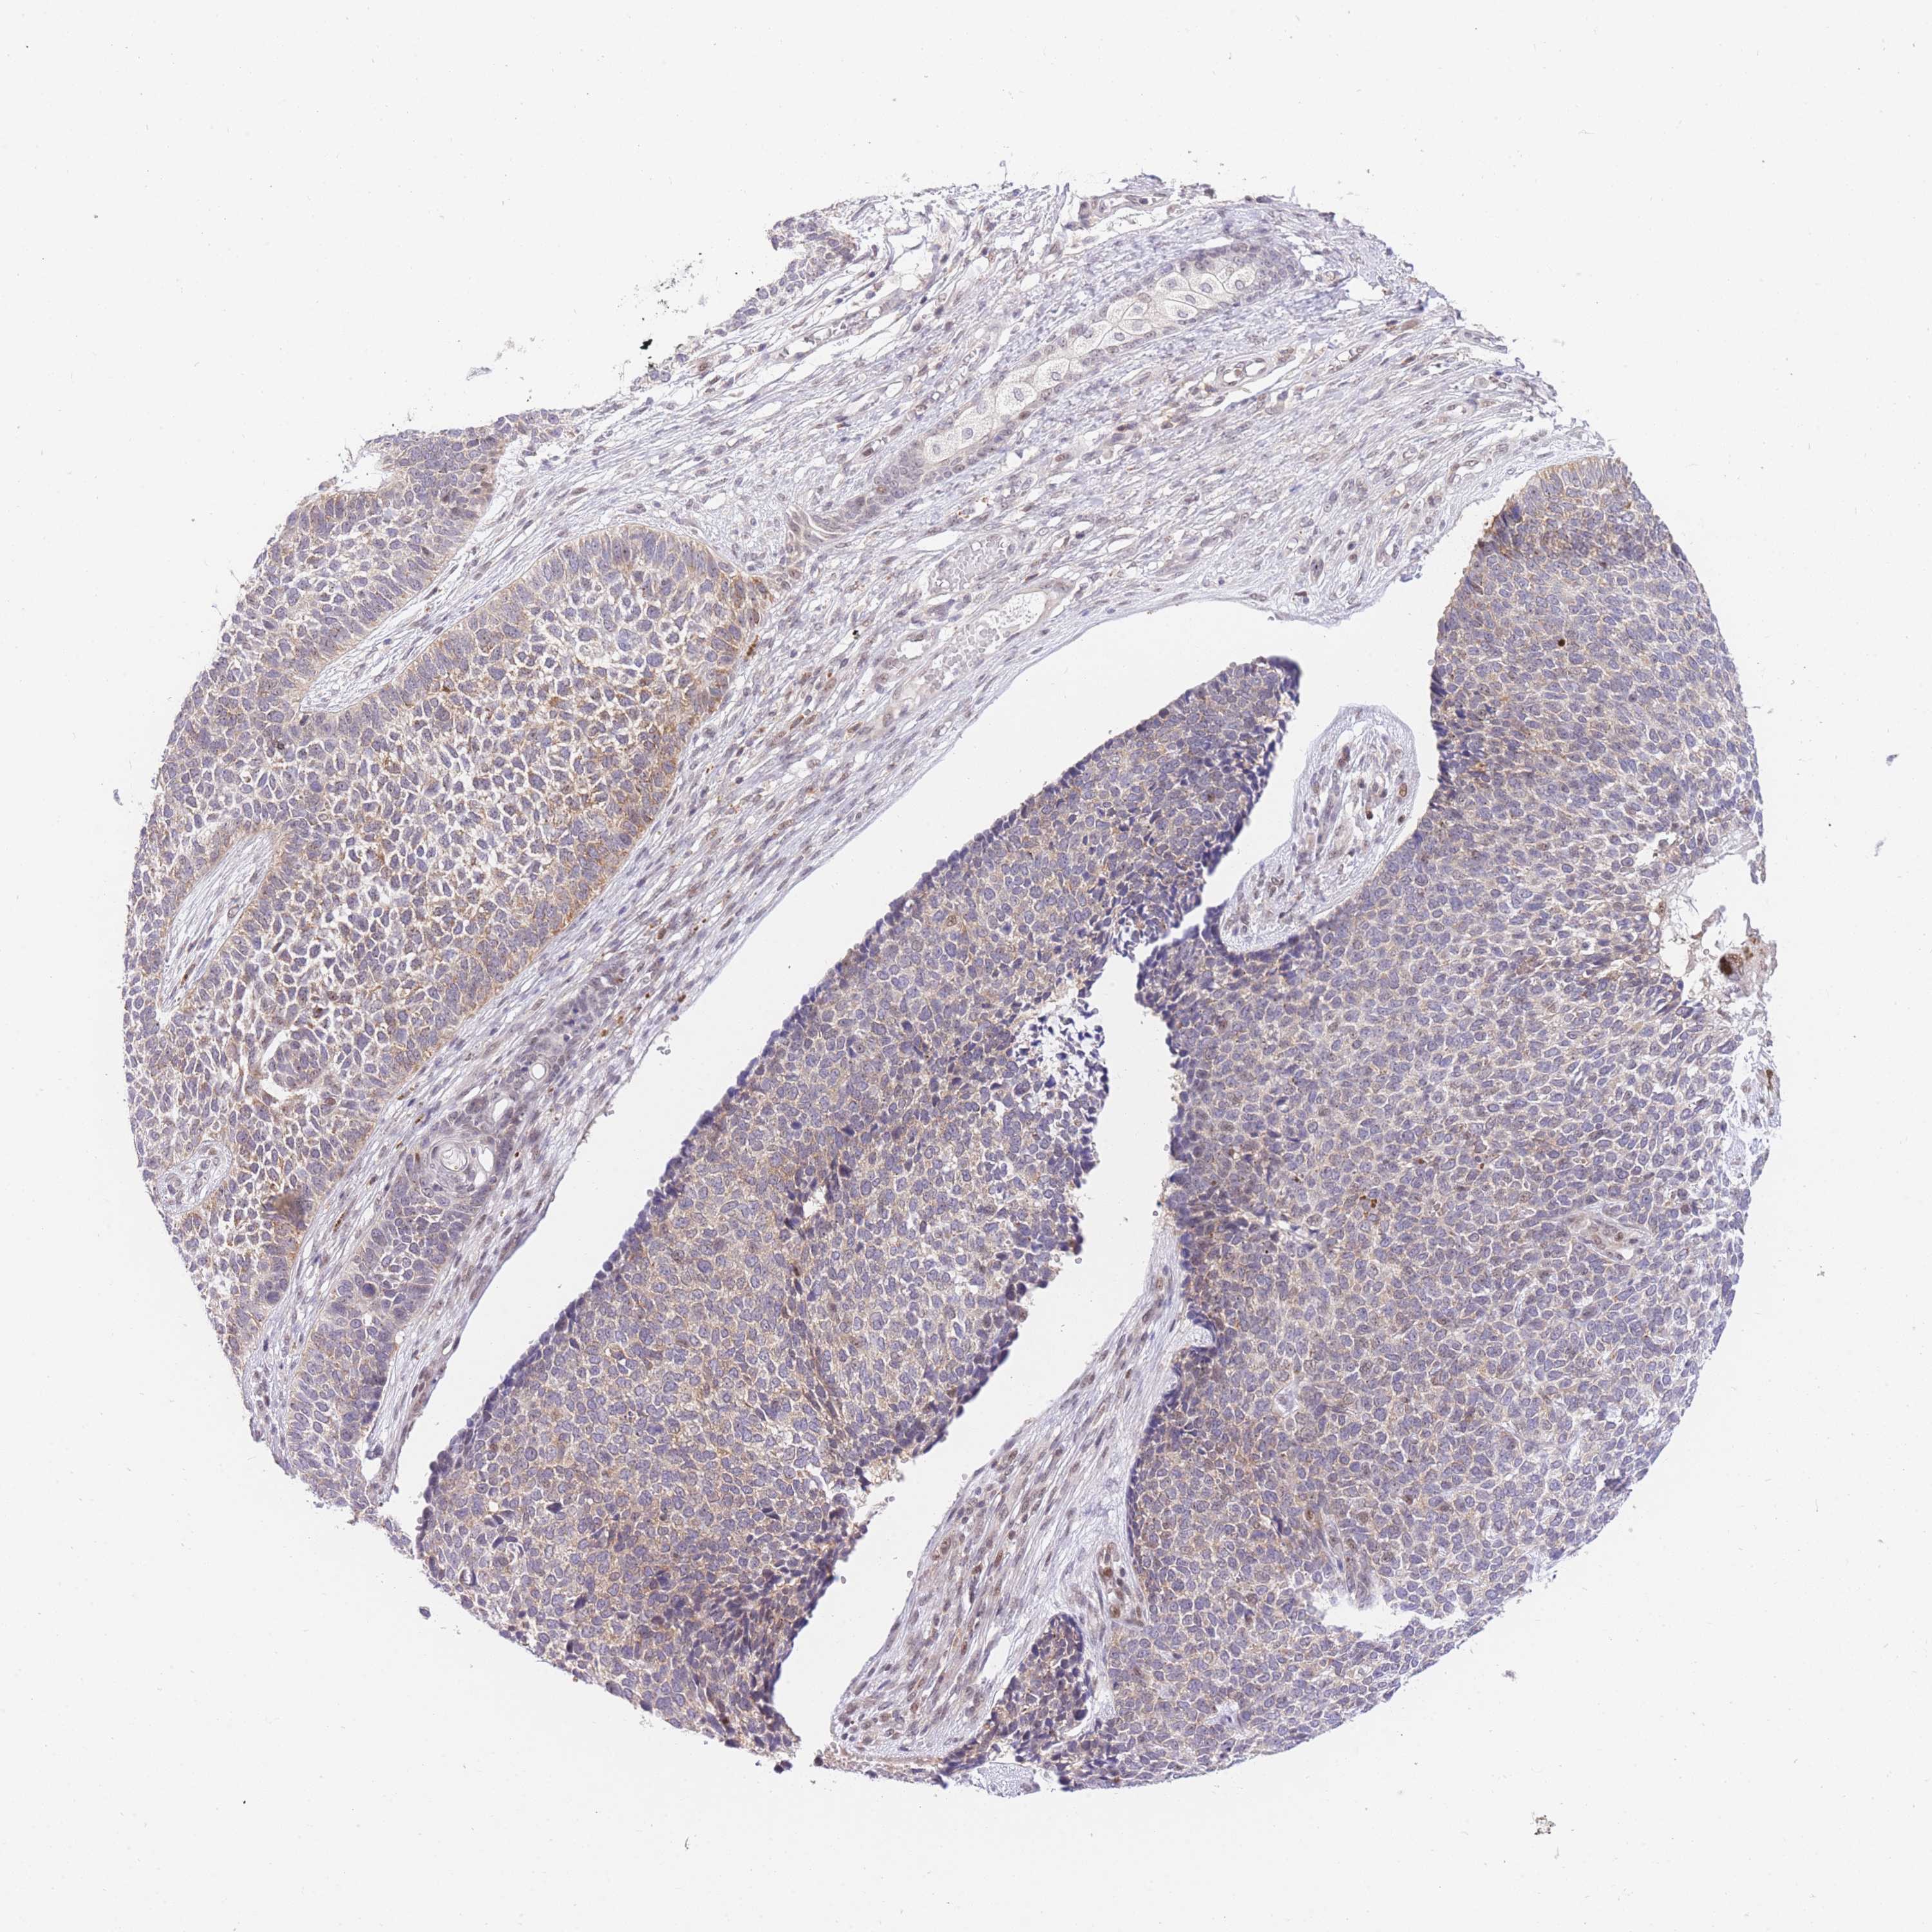

SKIN CANCER - Protein expressioni

A mouse-over function shows sample information and annotation data. Click on an image to view it in a full screen mode. Samples can be filtered based on level of antibody staining by selecting one or several of the following categories: high, medium, low and not detected. The assay and annotation is described here.

Each image is clickable and will lead to virtual microscopy that enables deeper exploration of all samples and also displays staining intensity scores, fraction scores and subcellular localization as well as patient and tissue information for each sample.

Antibody CAB046022

Squamous cell carcinoma, NOS